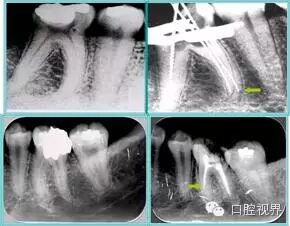

术后 X 线片用来评定根管充填 长度、致密度(管壁清晰、侧枝)等指标。

左图为根管充填术后 X 线片。图中可见,根管充填较好。右下图有白色小点,为侧方加压导致糊剂挤出所致,表明根管充填比较致密。

致密、恰到好处的充填可去除干净根管里感染灶,机体逐渐恢复。

多根牙时候需进行偏移投照,正位投照无法说明具体哪根牙根管充填效果。